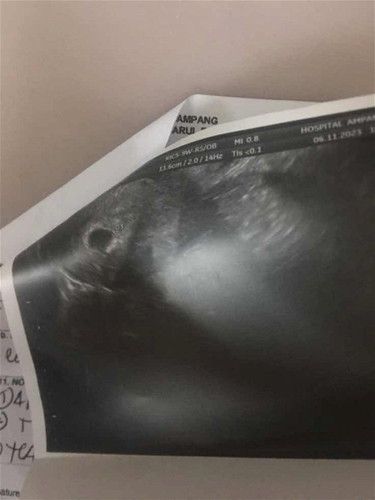

Nak tanya bagi kandungan 7w3hari dah boleh nampak janin ke??

assalammualaikum nak tanya sekarang usia kandungan saya 7w3h dah pergi epau untuk check tp nampak kantung je.. risau doktor bg lagi 1w lebih utk next appointment… doakan saya ada sahabat sume